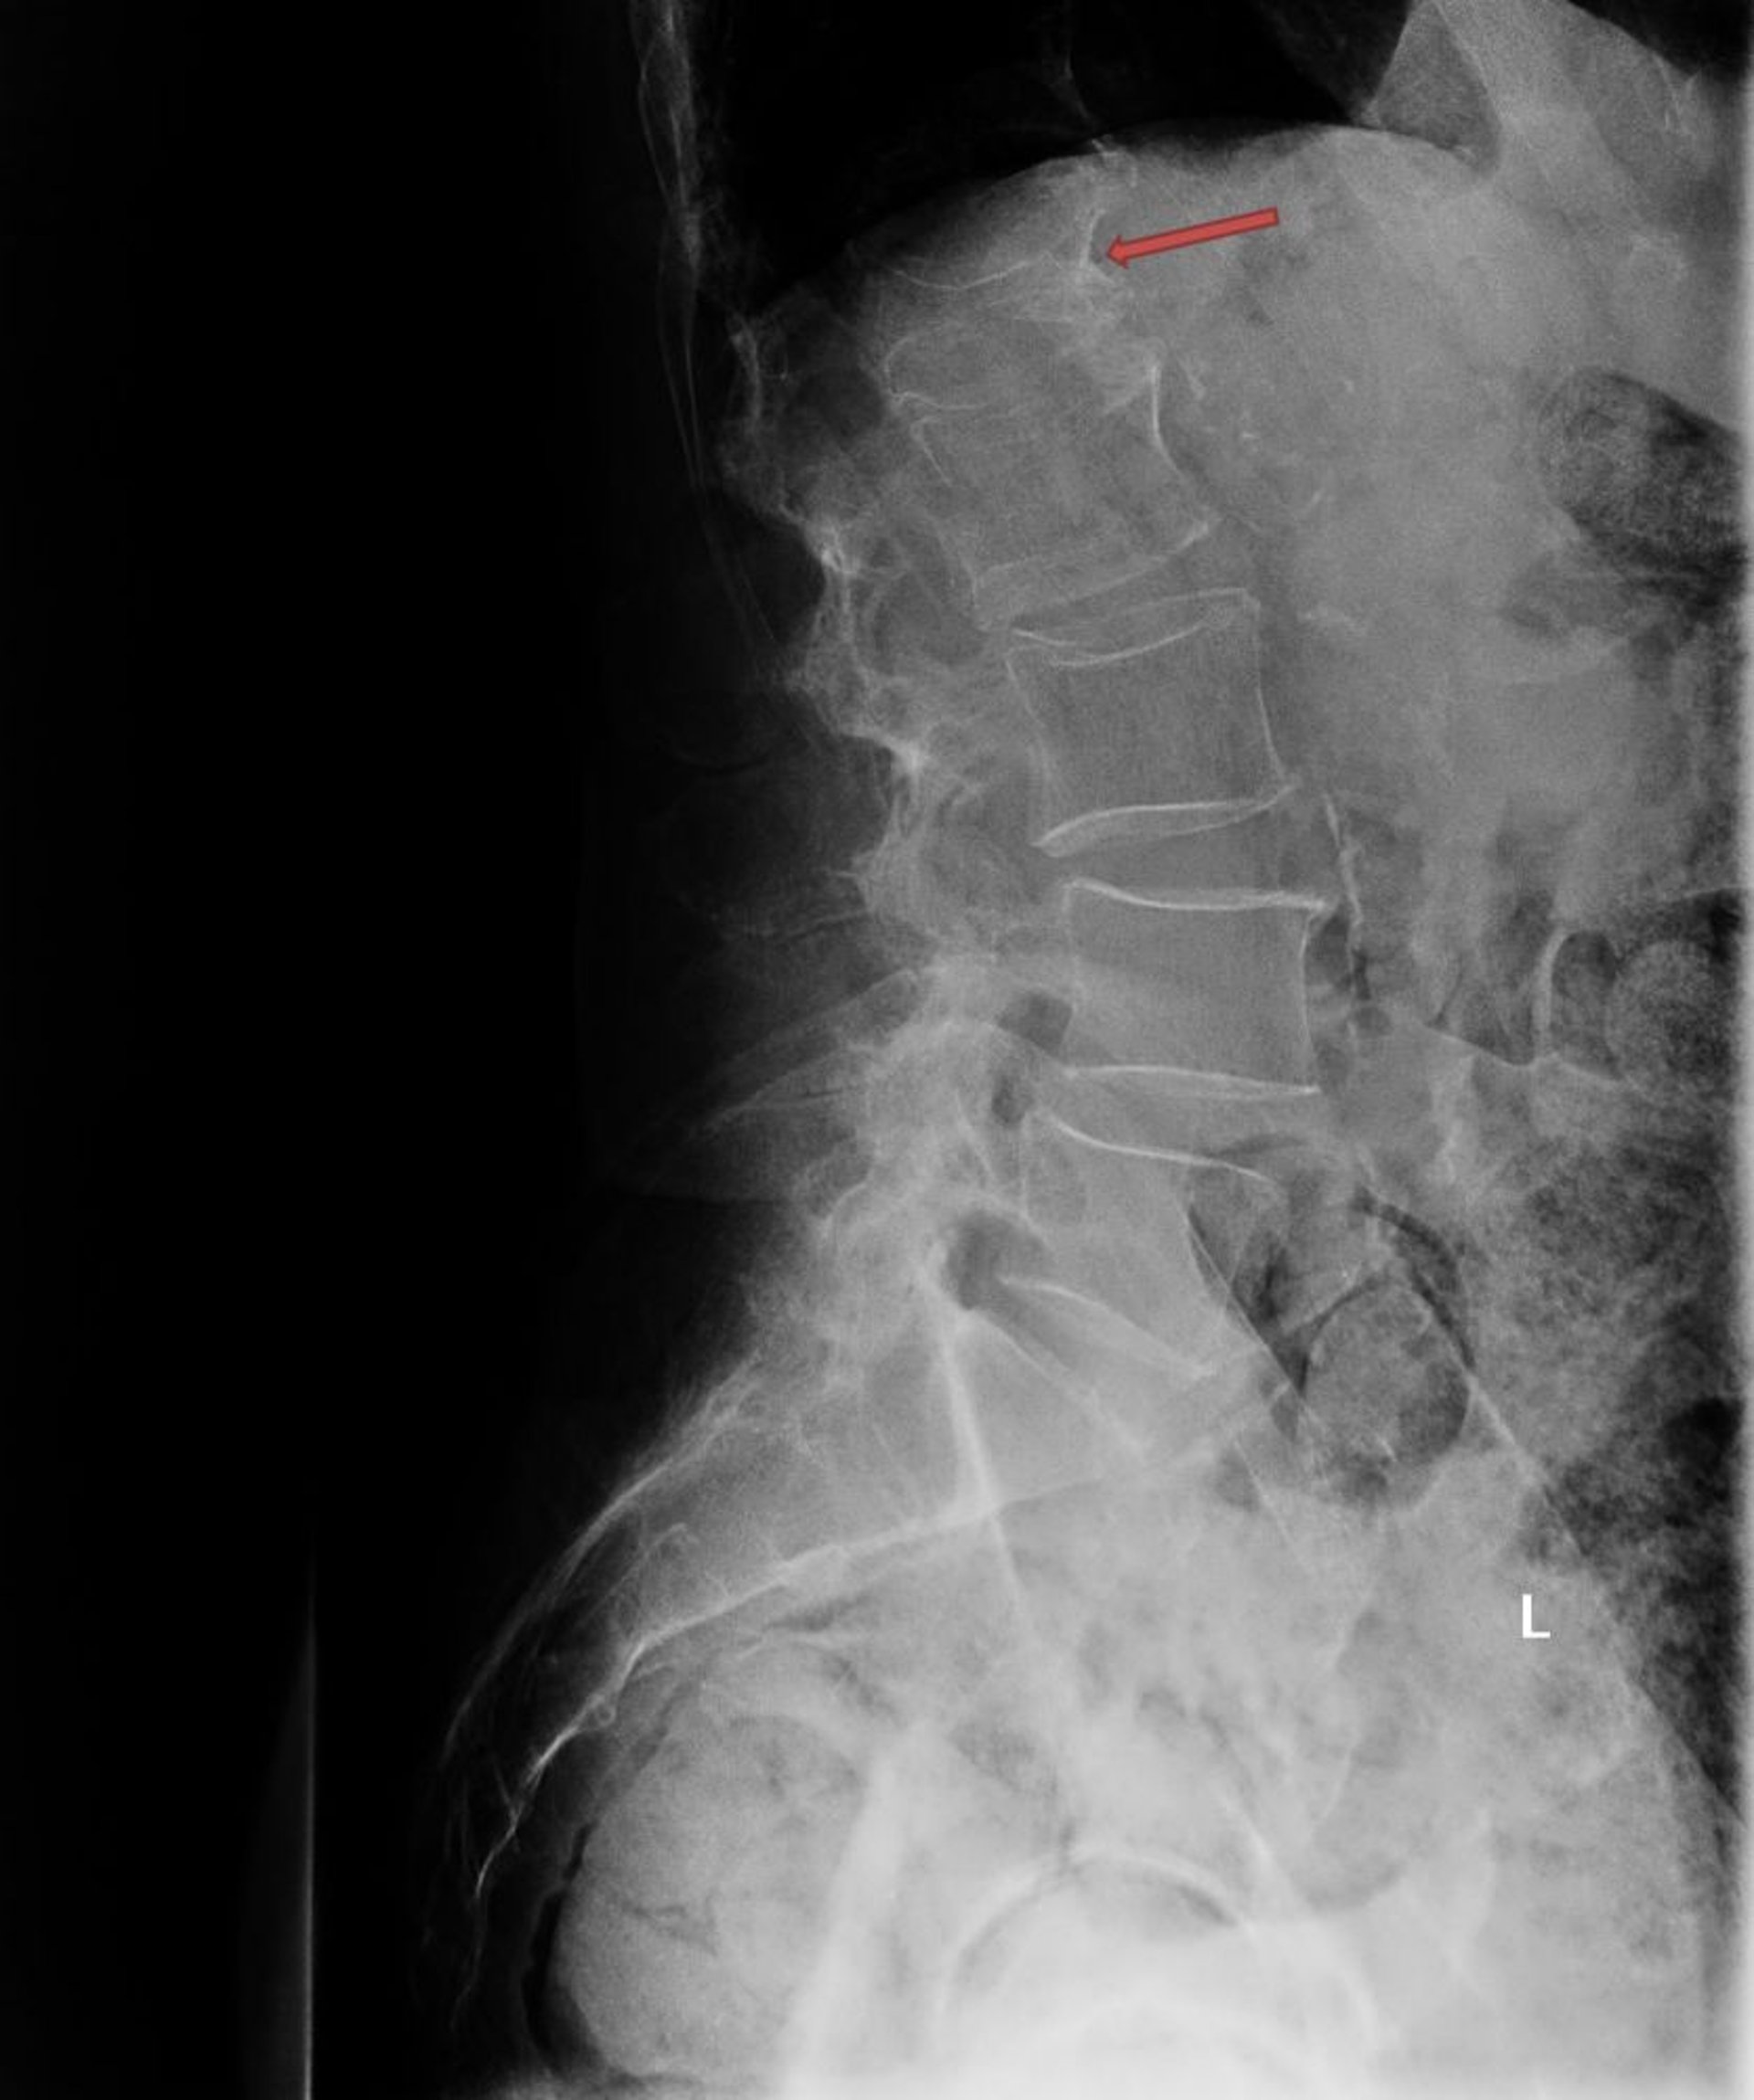

Fracture ostéoporotique par compression

Cette radiographie montre une fracture de compression ostéoporotique sévère de la première vertèbre lombaire (L1; flèche).

Photo courtesy of Marcy B. Bolster, MD.